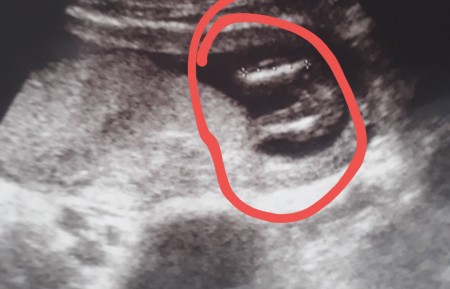

bebegin cinsiyeti ne zaman belli olur